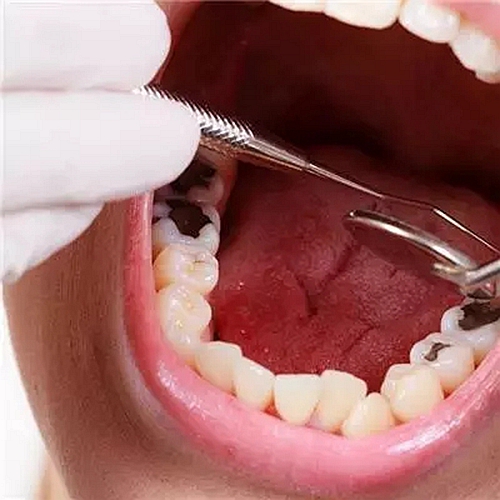

3、易發(fā)齲齒和牙齦炎

不用的那一側(cè)牙齒由于長期缺乏食物摩擦,而在牙齒間堆積大量的牙垢和牙石,容易發(fā)生齲齒并引發(fā)牙齦炎、牙周炎。